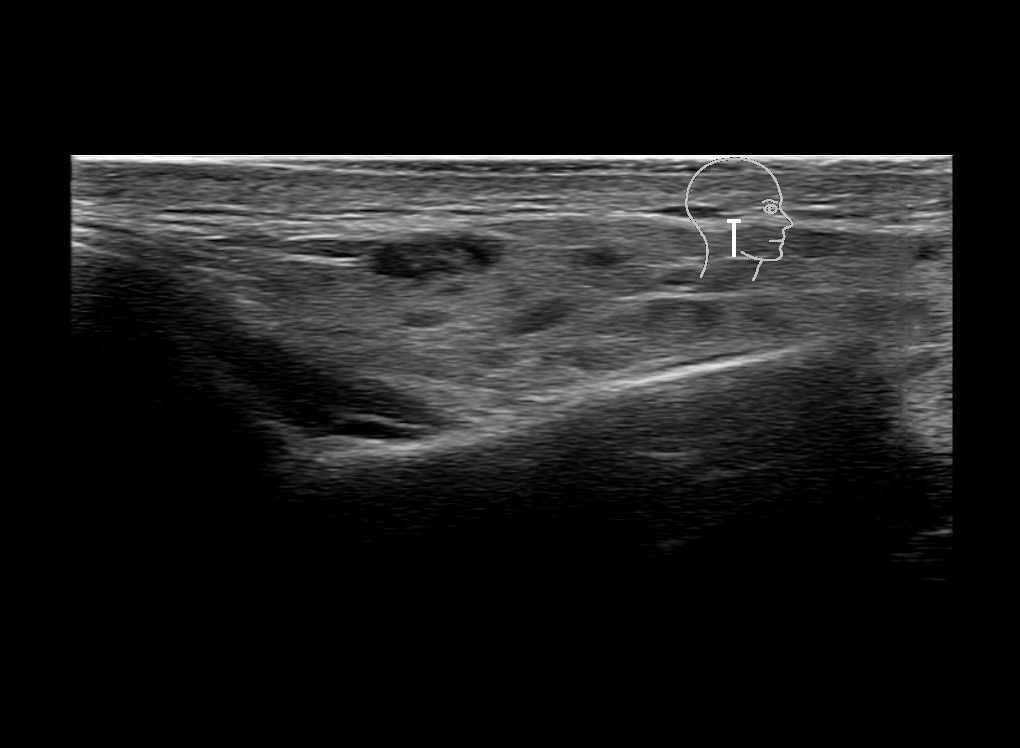

Study the first image to recognize the different layers. If you are sure about the layers, swipe to the second image to view the answer (if applicable).

Hover over an image to view the secondary image or click on the image title for more information.